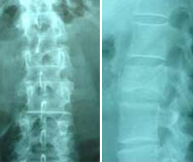

Mujer, 55 años. Fractura aplastamiento derecho de L2 . |